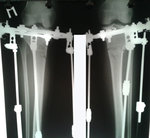

Дата операции 15.03.2017г.

Дата снятия аппаратов 23.06.2017г.

Срок лечения 97 дней.